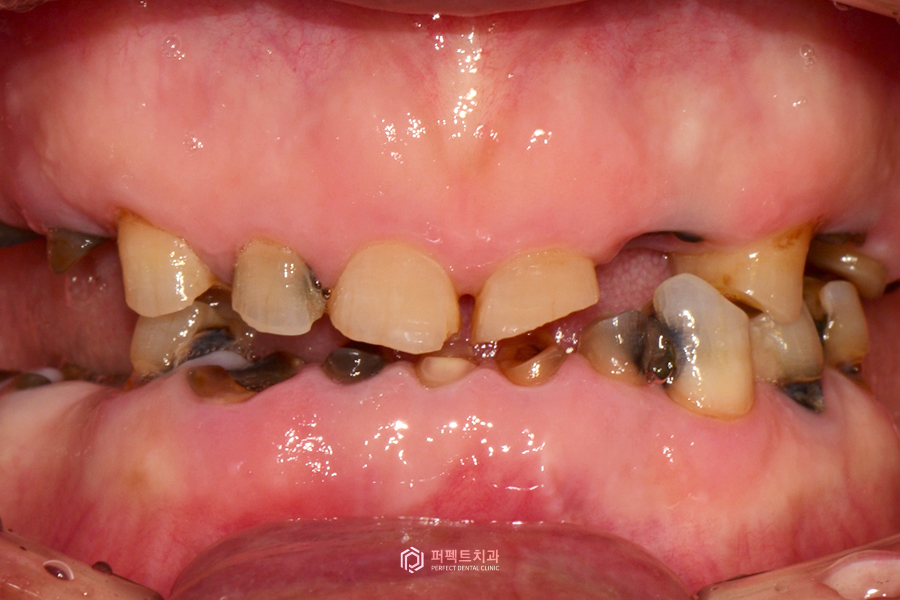

초진 구강사진

실제 구강 내 사진을 보시면 없는 치아들이 많고, 남아있는 치아도 모두 썩어있는 것을 보실 수 있습니다. 그리고 중요한 점은 치아가 계속 없이 지내게 되면 치아가 닳고 썩어서 교합이 무너진 상태입니다.

무너졌다는 것은 원래 씹는 높이가 정상이었는데 닳고 부러지면서 교합이 낮아져 있는 경우입니다. 이렇게 낮아진 교합 높이를 올리는 수복까지 다같이 이루어져야 해서 난이도가 높은 케이스에 해당하는 경우입니다. 이런 경우는 어떻게 해야 되냐면 임시치아 혹은 임시틀니를 이용해서 그 높이를 맞춘 다음에 거기에 맞는 최종보철을 만든 그런 경우라고 보시면 될 것 같습니다.